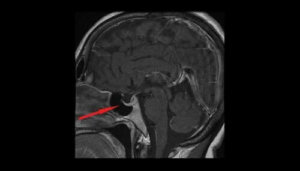

Diagnose

Een arts moet een lichamelijk onderzoek uitvoeren om te analyseren of er problemen zijn met het gezichtsvermogen, zoals dubbel zicht. Ook bestuderen laboranten het verlies van gezichtsveld en het vermogen om te zien in bepaalde gebieden.

Vervolgens voeren ze een analyse uit van de endocriene functie om te zoeken naar tekenen van een overschot aan hormonen of andere onregelmatigheden.

Zo kunnen ze verhoogde cortisolniveaus meten, onderzoek doen naar het syndroom van Cushing of overschot aan groeihormonen. De meest relevante tests die de diagnose helpen bevestigen zijn tests van het gezichtsveld en een hersenscan.